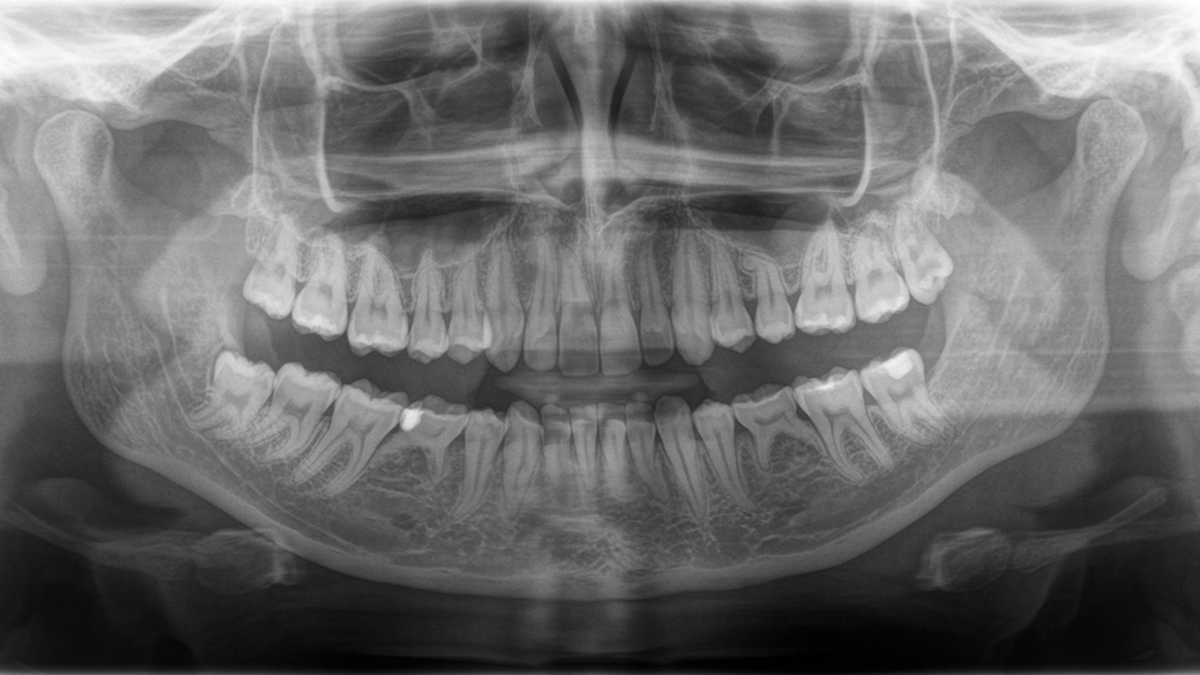

Panoramic image quality is constantly evolving

To the left: 10-year-old PAN image. To the right: DCS image taken with Orthophos SL